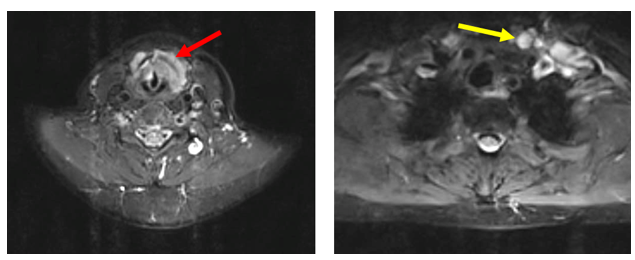

- MRI vùng cổ (T1/2025)

Hình 1: Khối xâm lấn vùng hạ họng – thanh quản kích thước 41 x 22 mm (mũi tên đỏ), hạch cổ 2 bên, hạch lớn nhất đường kính 10 mm (mũi tên vàng).